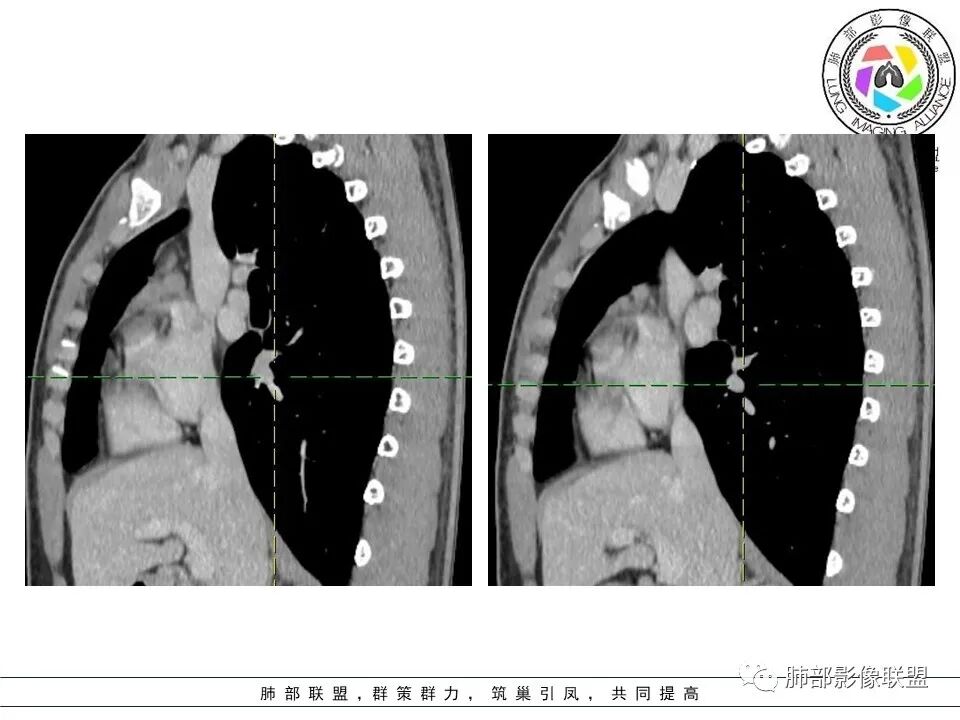

16岁男性,体检发现纵隔病变,提示无症状

前纵隔胸腺区病变

按分叶一边一个

大家看看这病灶信号

边界清吗

看看这个内部结构

是分叶还是两个病灶?

两个

两部分

多个病灶

但是结构疏松,边界不清:

问题是不是都是结节状,部分是条带状

胸腺内的

多发病灶

从MR看结构松散

不太符合肿瘤

首先考虑非肿瘤性病变

关键在于其结构松散,外周密度增高,周围渗出

整体形态没有肿瘤的特点,特别是MR

就觉得内部结构松散

无肿瘤的特点